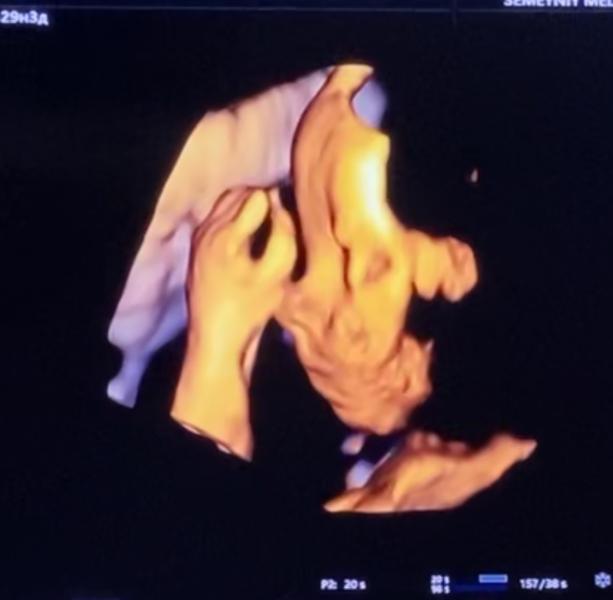

Привет 👋 #декрет #30недель 😁 Наконец-то мы добрались до УЗИ и увидели малышку 😍она такая забавная, все время улыбалась, потом закрылась ручкой и отвернулась 😁типа хватит 👌😉 Врач узи сказала- какая симпатичная малышка 🤗😍😉👌выходим на финишную прямую🙏🏼